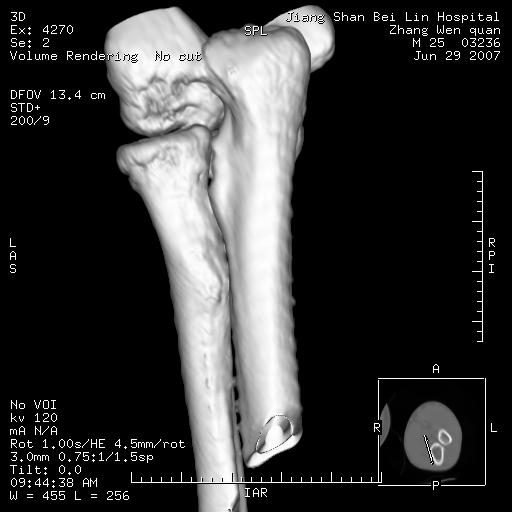

标题: CT8866:男27岁,正常吗?

患者男27岁,2007年3月查出患上肘关节滑膜结核,此后行手术滑膜剥除,今查ct

看一下上面的桡骨粗隆有问题吗?

桡骨粗隆有问题,术后改变

桡骨骨皮质破坏,结合病史考虑结核